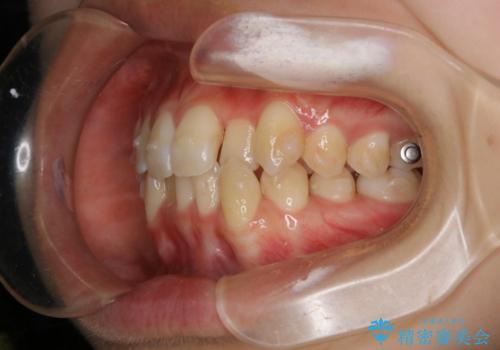

下顎前歯の先天欠損と上顎前歯のクロスバイト:インビザライン治療

- 上の前歯が1本後ろに入ってしまっていることが気になるとご相談にいらした方です。

元々下の前歯が1本欠損しており、上下の噛み合わせや、歯のサイズバランスを考慮しながら治療を行いました。

クロスバイトしている歯が深く噛み込んでおり、この歯を外に出してくる際に強い咬合力が加わると歯が失活する恐れがあることを説明し、合わせて咬筋へのボトックス注入を行いました。

下顎切歯が1本欠損しているため、上顎前歯部を少しずつストリッピングして、上下の噛み合わせ、バランスの向上を図りました。